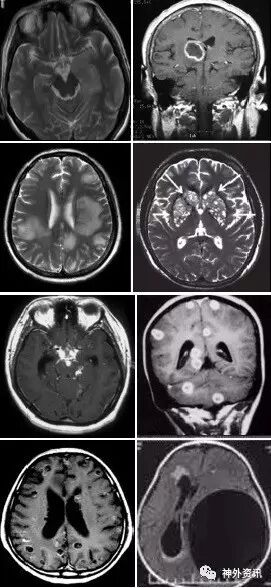

(重要申明:以下每个部分会配磁共振图片,因疾病和影像之间存在同病异象、同像异病,为避免误导,图片不标注疾病,其各自鉴赏,另其中的部分图片来源于网络,有疑问可与本人联系)

如酒精中毒相关的,如MBD。

各种中毒,有机溶剂,如苯、甲醇、一氧化碳中毒、氨己烯酸中毒等。

毒品如海洛因、可卡因等。

抗肿瘤或免疫抑制剂如甲硝唑、5-FU(5-氟尿嘧啶)及其前体药物卡培他滨、他克莫司、甲氨蝶呤、贝伐单抗等相关性脑病。

各种动脉性、静脉性血管病、静脉窦血栓形成、动脉夹层致脑梗塞、脑小血管病、脑动静脉畸形、CAA等,Moya-Moya也可出现脑实质的多发病灶,易被误诊为脱髓鞘。

除此之外,还有一些解剖结构变异造成的病变,如V-R间隙扩大,灰质异位等。